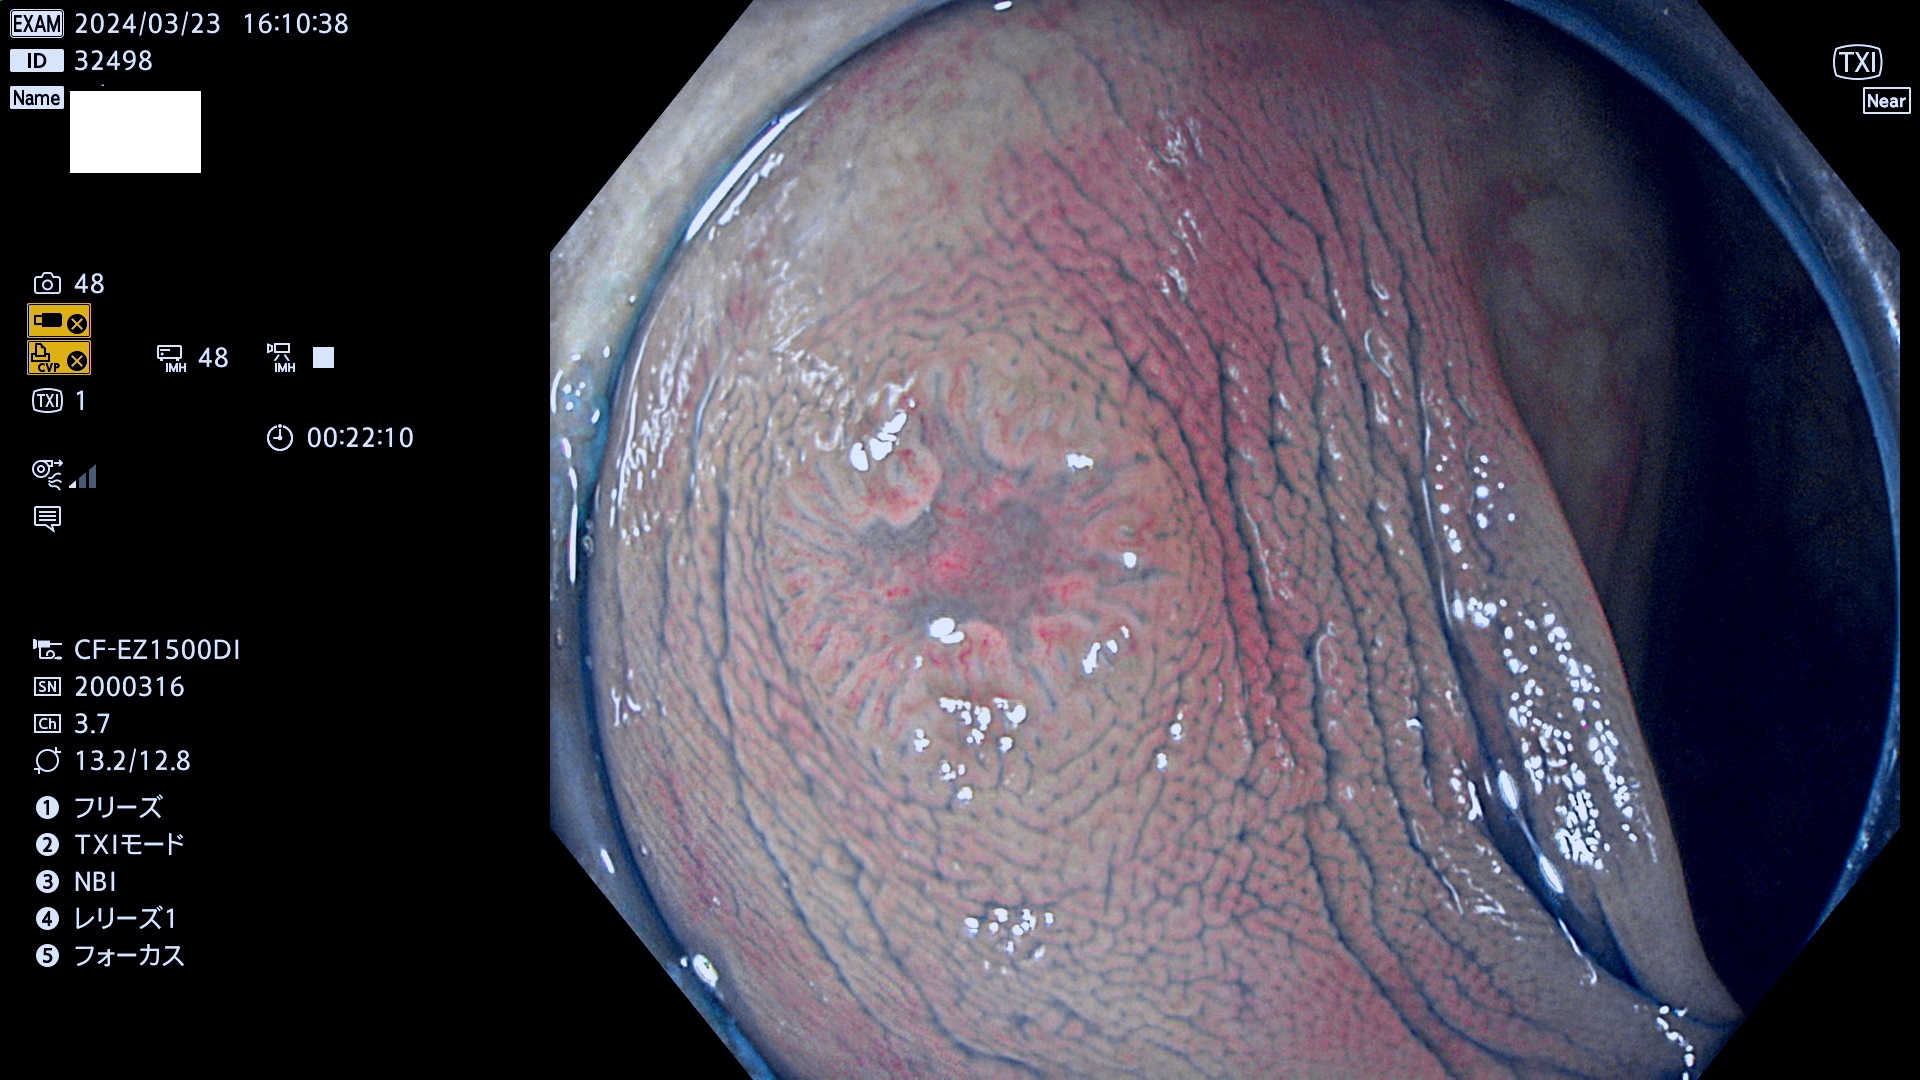

表面型腺腫(Flat Adenoma)の中で、完全に平坦な物をUb、陥凹している物をUcと呼びます。平坦隆起型(Ua)よりも、発見が難しく危険な病変です。

毎週の検査(木・金・土・日)に発見されたUb、Uc型・腺腫を、その週の日曜の夜にUPし1週間、提示します。

抽出の対象期間 2024年3月21日(木)〜3月24(日)の4日間(44件の検査)7件 (8/44=18%)